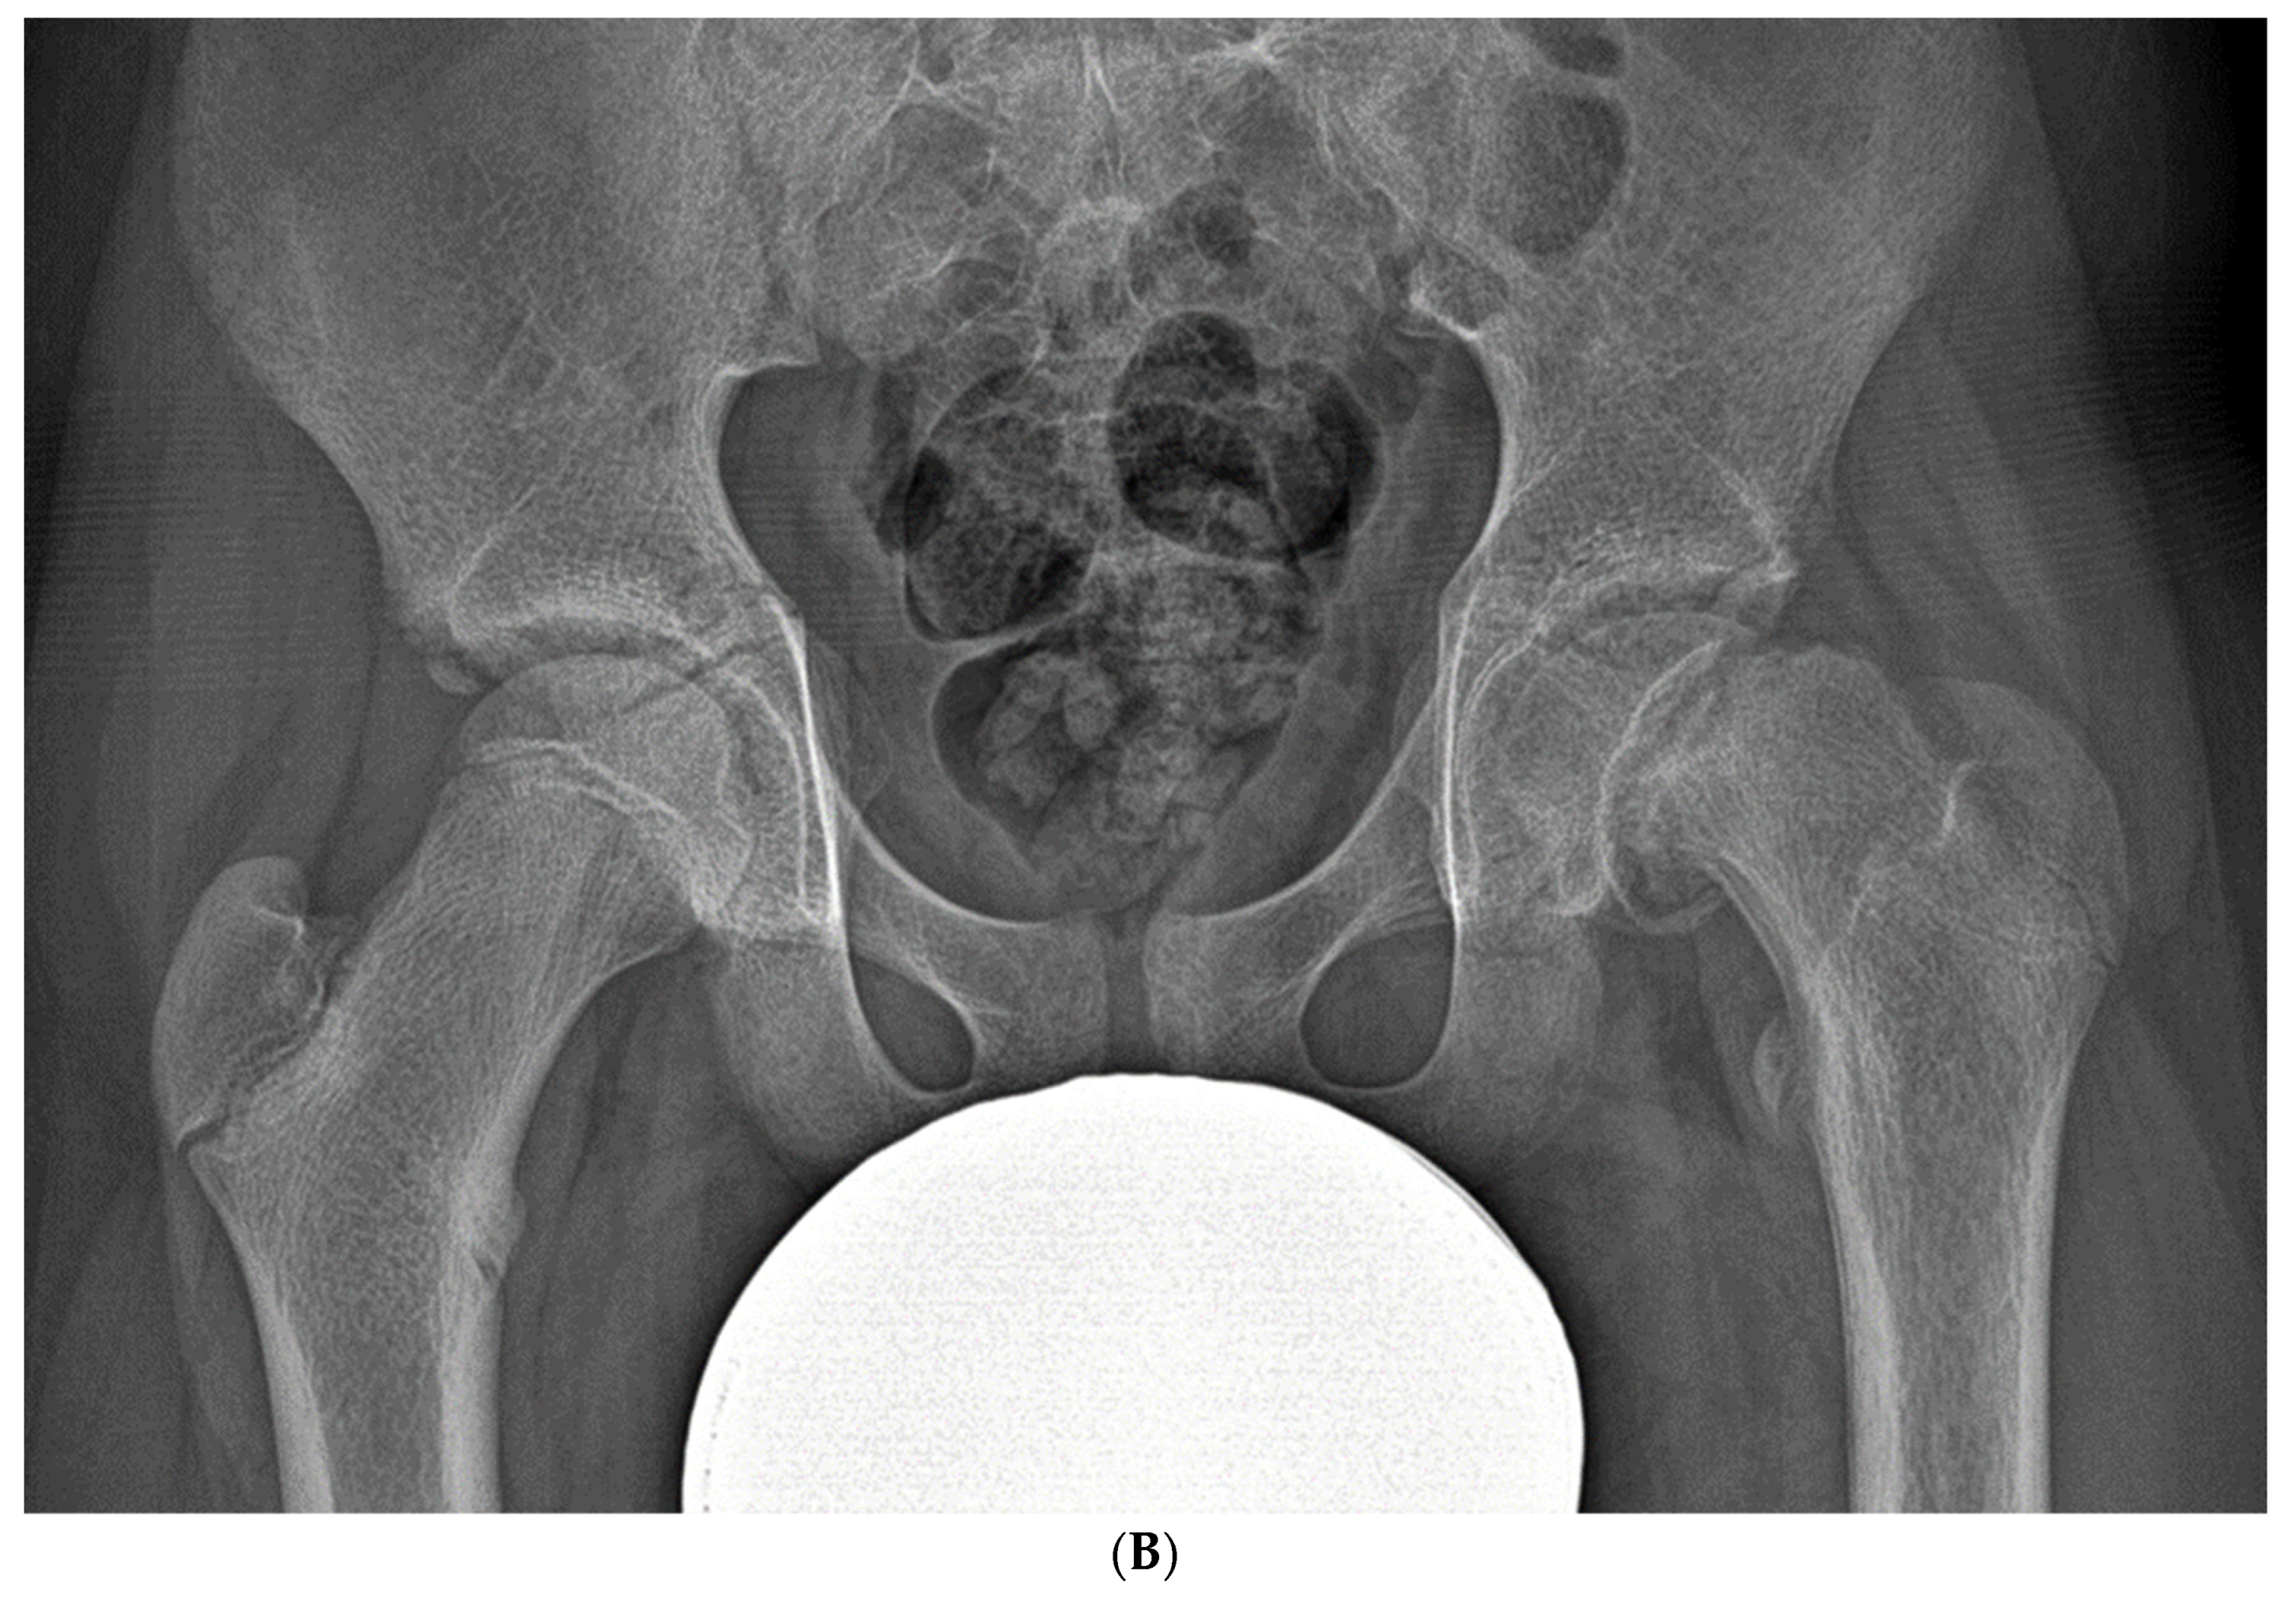

3.2.4. Exfoliation of Growth Plates